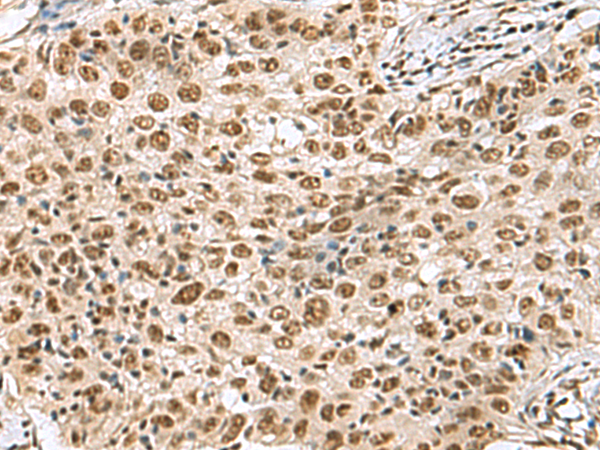

分类: 科研抗体货号: P03228别名: RAY应用: IHC反应种属: Human, Mouse, Rat